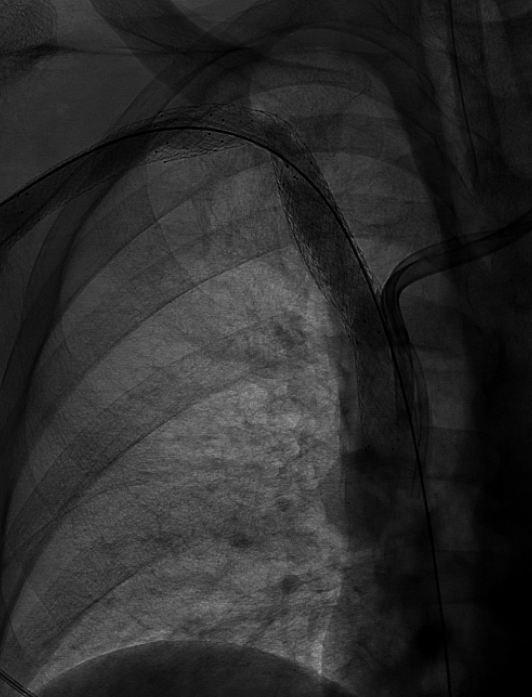

Renal AVM causing a varicocele and Dyspnea- embo X 2 1. AVM-AVP &coils 2. varicocele- STS&AVP -dyspnea resolved on the table #irad SIR RFS

Renal AVM causing a varicocele and Dyspnea- embo X 2

1. AVM-AVP &coils

2. varicocele- STS&AVP

-dyspnea resolved on the table #irad <a href="/SIRRFS/">SIR RFS</a>